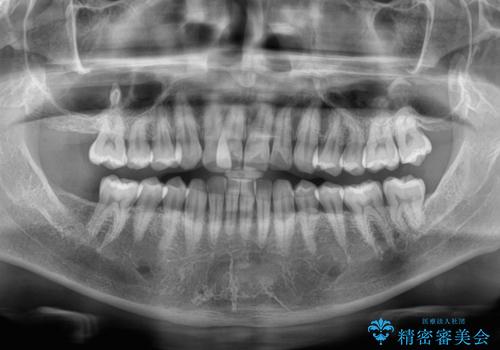

- 上下前歯のデコボコを気にして来院された患者様です。

ワイヤー矯正でもマウスピース矯正でも可能でしたが、短期間で、自身の手を煩わせることなく治療を行いたいとのことで、ワイヤー装置にて矯正治療を行うこととしました。

上顎前歯の舌側転位が顕著であったため、治療期間が長くなると思われましたが、僅か1年で無事に終えることができました。